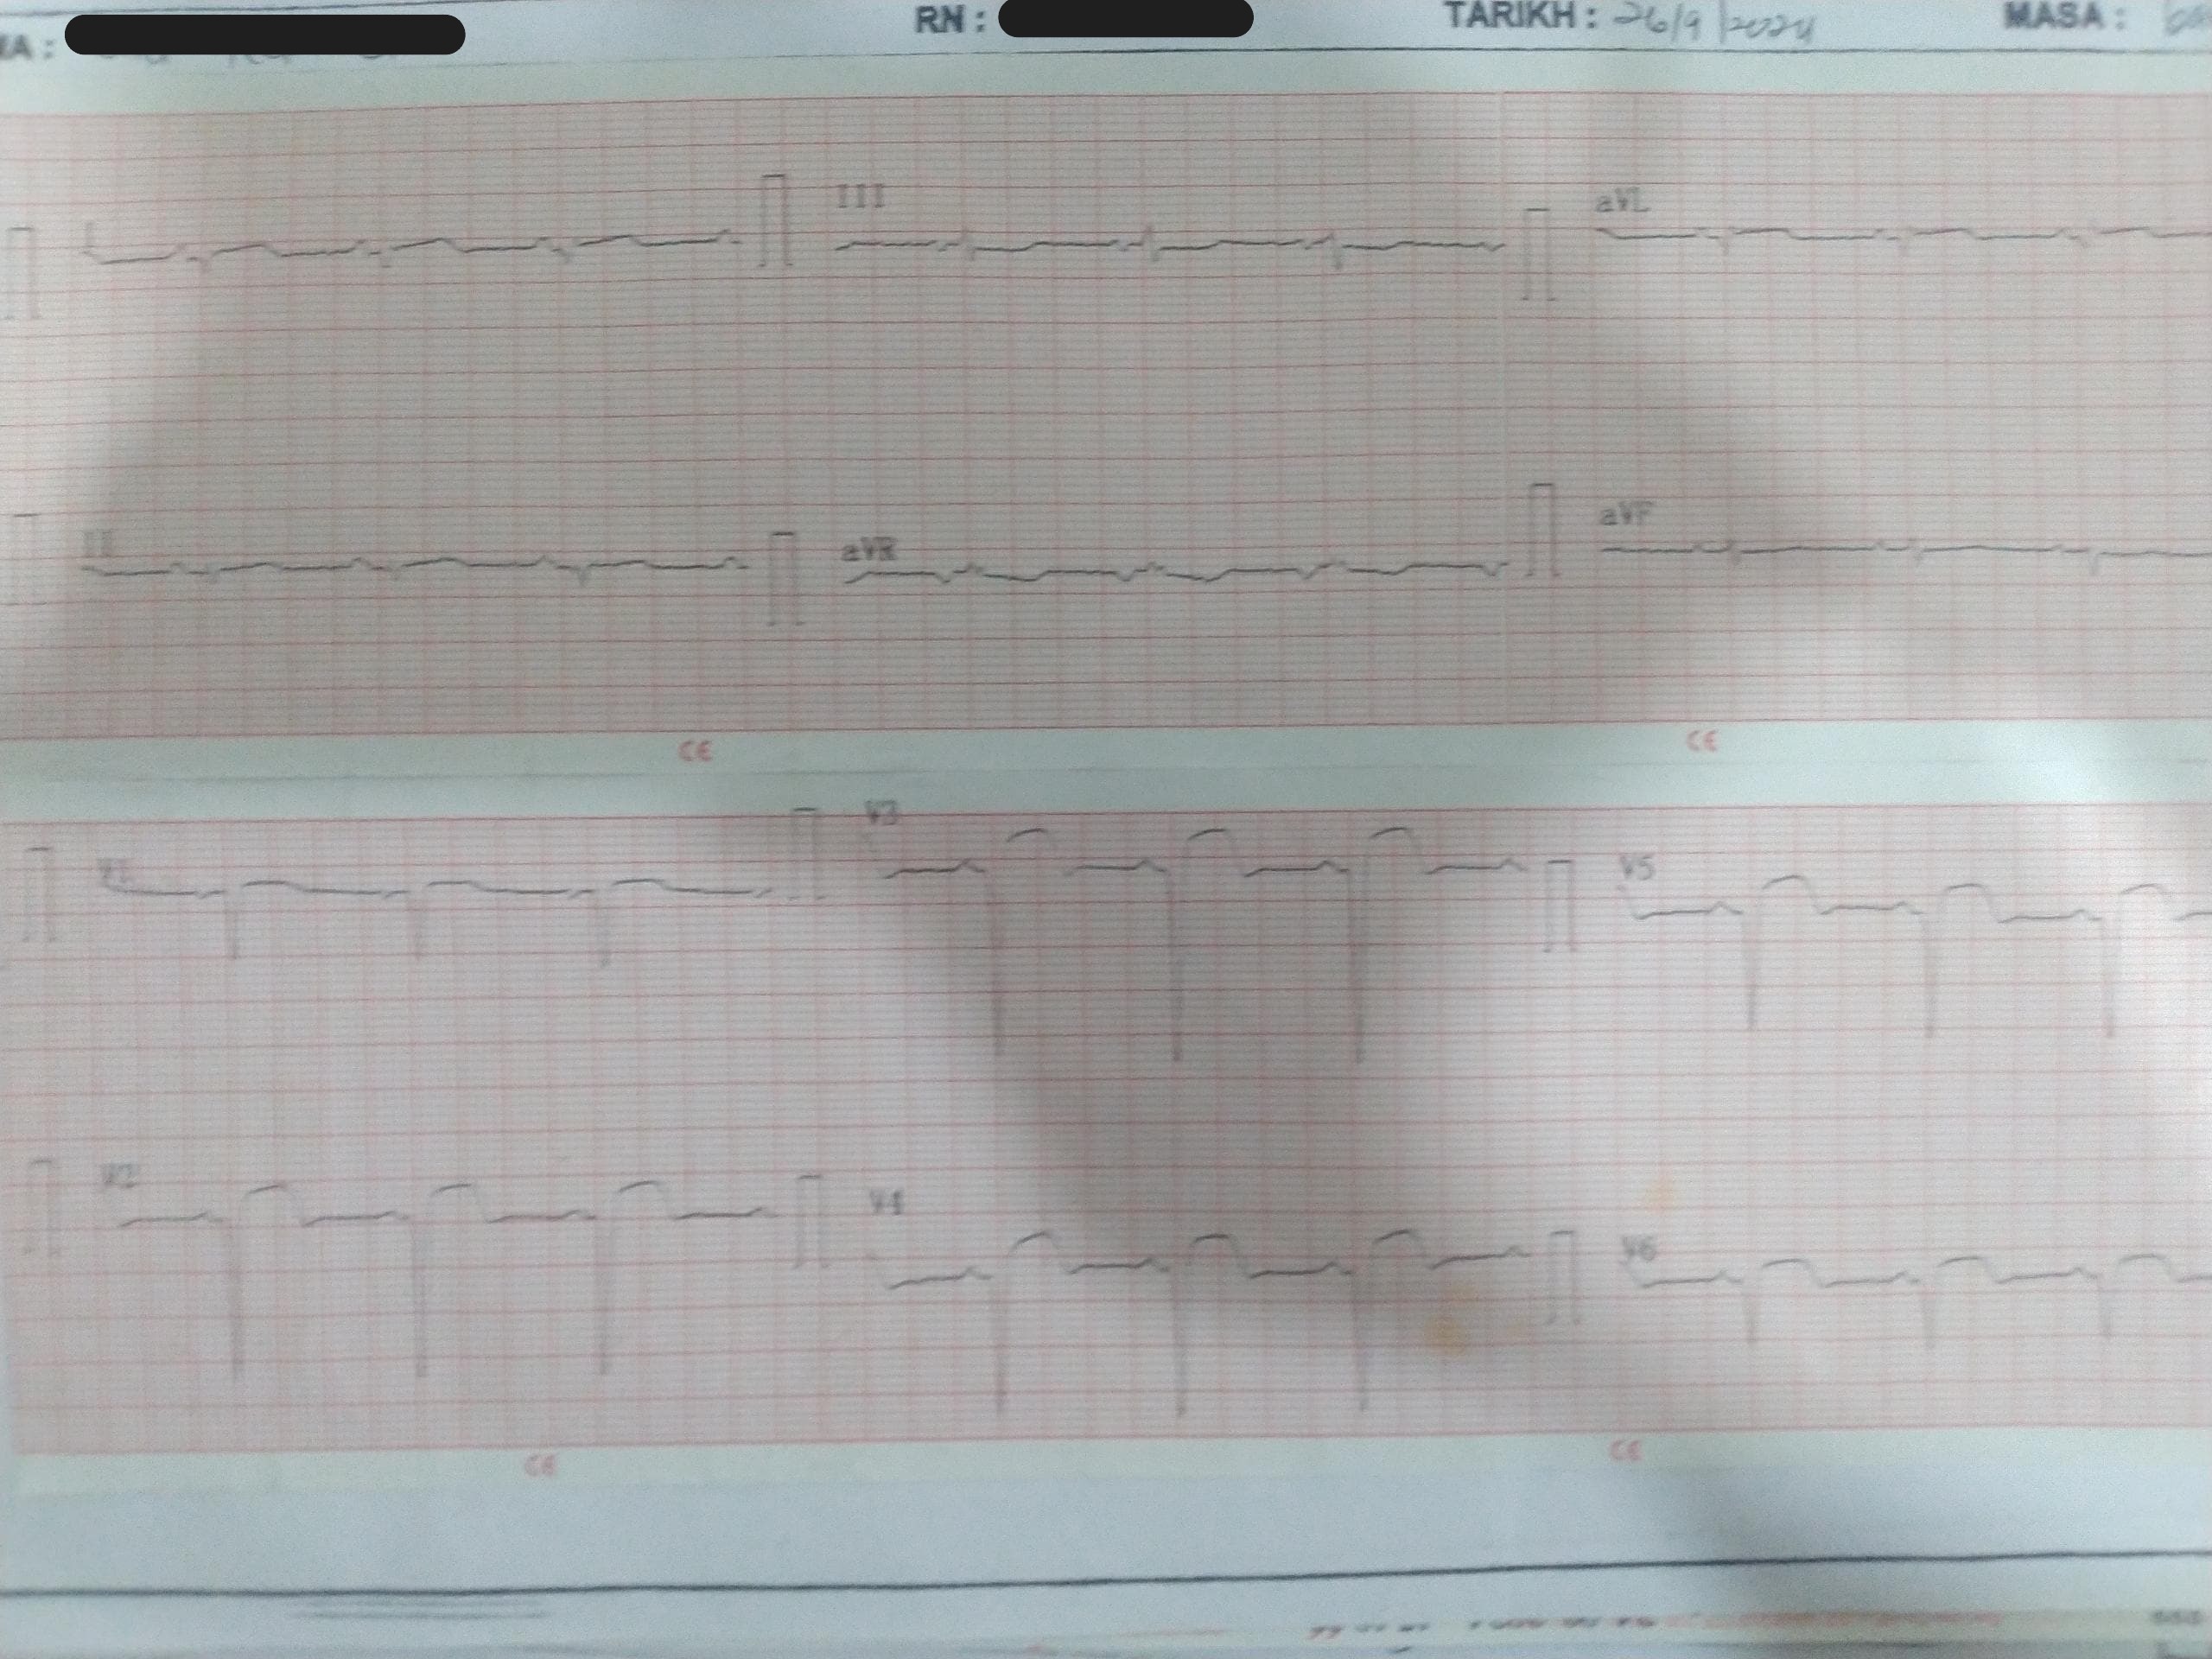

Relevant Test Results Prior to Catheterization

His electrocardiogram on admission showed sinus rhythm with deep Q wave over lead V1 to V6 with ST elevation of 3mm. His Trop T was 78454 ng/L and creatinine kinase was 692 U/L. His lactate dehydrogenase was 1256 U/L. He had mild acute kidney injury with creatinine level of 114 micromoles/L. His total cholesterol was 4.5mmol/L and low density lipoprotein was 2.8 mmol/L. The fasting blood glucose level was 3 mmol/L. Otherwise, the liver function test and electrolytes levels were unremarkable.